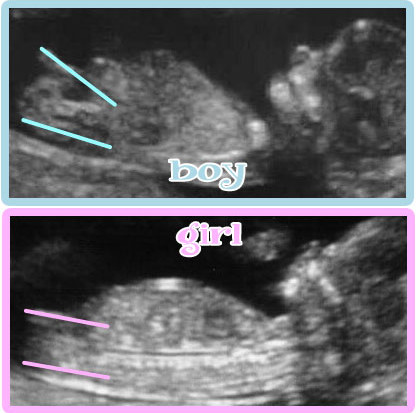

Met 12 weken deed ik bij het echo bureau de nekplooimeting voor de combinatietest. Hier kwam deze nub theorie opeens ter sprake. De mevrouw van het bureau gaf aan dat ze met de nub theorie kon zien wat het wordt. Ze gaf meteen aan dat deze theorie absoluut niet 100% zekerheid geeft maar dat de kans wel groot is. De vraag dus of ik het zou willen weten. Dit vond ik een lastige. Ik ben namelijk enorm nieuwsgierig van aard maar mijn man was niet bij de echo en dit is wel iets wat je wilt delen met je partner. Daarnaast weet ik niet of het fijn is iets te weten waar je eigenlijk niet zeker van kan zijn. Ik heb haar darom gevraagd het in een envelop te zetten zodat ik ‘s avonds samen met mijn man kan besluiten om het wel of niet te bekijken.

Hier staat een korte uitleg van de nub theorie.